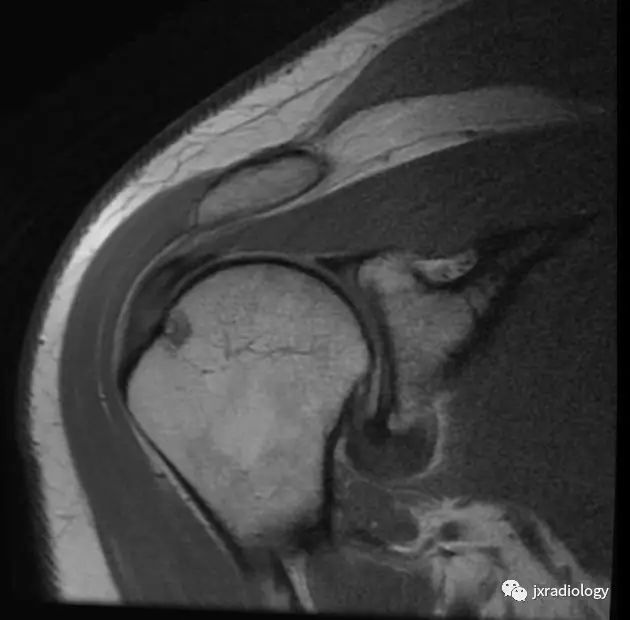

腋囊的增厚和水肿

肩袖间隙异常软组织信号(细箭)

腋囊增厚和水肿(细箭)

腋囊增厚纤维化(T1/T2均为低信号):

MRI关节囊造影提示腋囊体积缩小:

• 正常下盂肱韧带测量值<4毫米,在斜冠位上关节囊中间层面显示最好;在粘连性关节囊炎患者中,腋隐窝软组织增厚≥1.3厘米

• 关节囊增厚

• 肩袖间隙异常软组织增厚伴信号异常

• 异常软组织包绕肱二头肌腱

• 增强后腋隐窝和肩袖间隙的关节囊或滑囊强化

其他MR关节造影包括

• 喙肱韧带(CHL)增厚

• 喙突下三角征

• 腋囊正常容量15-18ml,本病小于10ml,多数小于5ml(文献上)